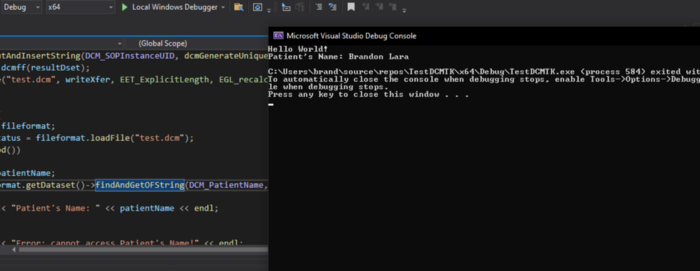

Then we run the TestDCMTK project using Visual Studio:

If everything went well, you should have created the test.dcm file in the project folder containing the .cpp file and where the test image was placed.

- Using the DCMTK libraries we can write the following code to display the patient’s name on the console:

In my case, the result of executing this code is: